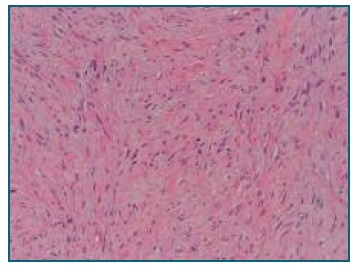

Gross examination of the specimen showed a 20 x 17 x 12 cm mass with 2085 g. Macroscopically, the tumor was firm and the cut surface was white and trabeculated, resembling scar tissue (Figure 2). Proliferating slender spindle-shaped cells separated by abundant collagenous stroma (Figure 3) were found in histology. Polymerase Chain Reaction analysis was positive for CTNNB1 gene mutation, favoring the diagnosis of a desmoid-type fibromatosis.

Figure 3 Lesion microscopy - Low magnification hematoxylin and eosin stain: spindled - stellate tumor cells with ill-defined borders, fibrillary eosinophilic cytoplasm, and bland nuclei.